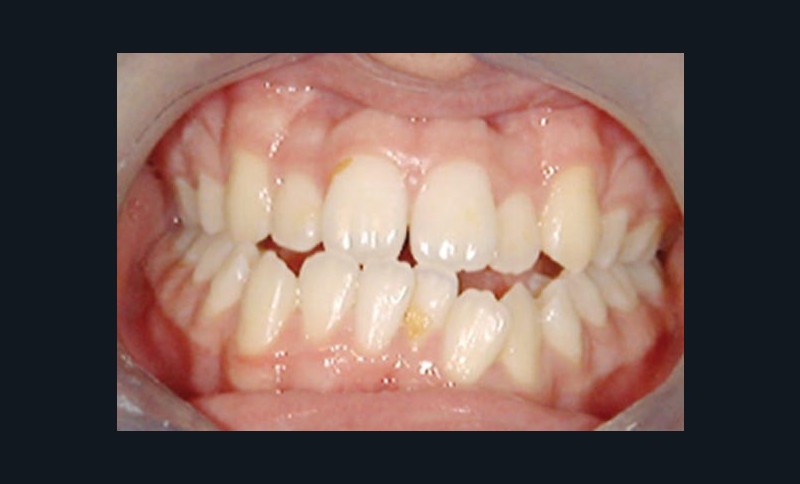

Olivier se présente à l’âge de 12 ans avec une classe III squelettique à prédominance mandibulaire, accompagnée d’une hyperdivergence et d’une endomaxillie responsable des inclusions des canines supérieures à forte obliquité. Une phase d’expansion est réalisée afin de permettre une augmentation du périmètre de l’arcade et la verticalisation des germes des canines. L’expansion permet en effet une normalisation transversale mais ne permet pas de réaliser la mise en place des canines. Les extractions des prémolaires sont alors effectuées et une préparation primaire de l’arcade supérieure par multi-attaches avec désinclusions et tractions des canines est réalisée.